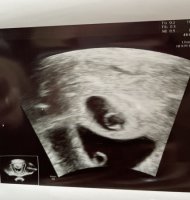

Åja, bare 6-7 ja...det var trist. Men fosteret og morkake flytter jo ikke på seg på de 14 dagene eller? Hmm, ble forvirret jeg nå. Men stemmer det at plasseringen hos meg tilsier gutt?Tror Uke 9 er for sent å bruke ramzi.. skal brukes i uke 6-7 helst

Dette bildet er fra innvendig mellom uke 7 og 8.